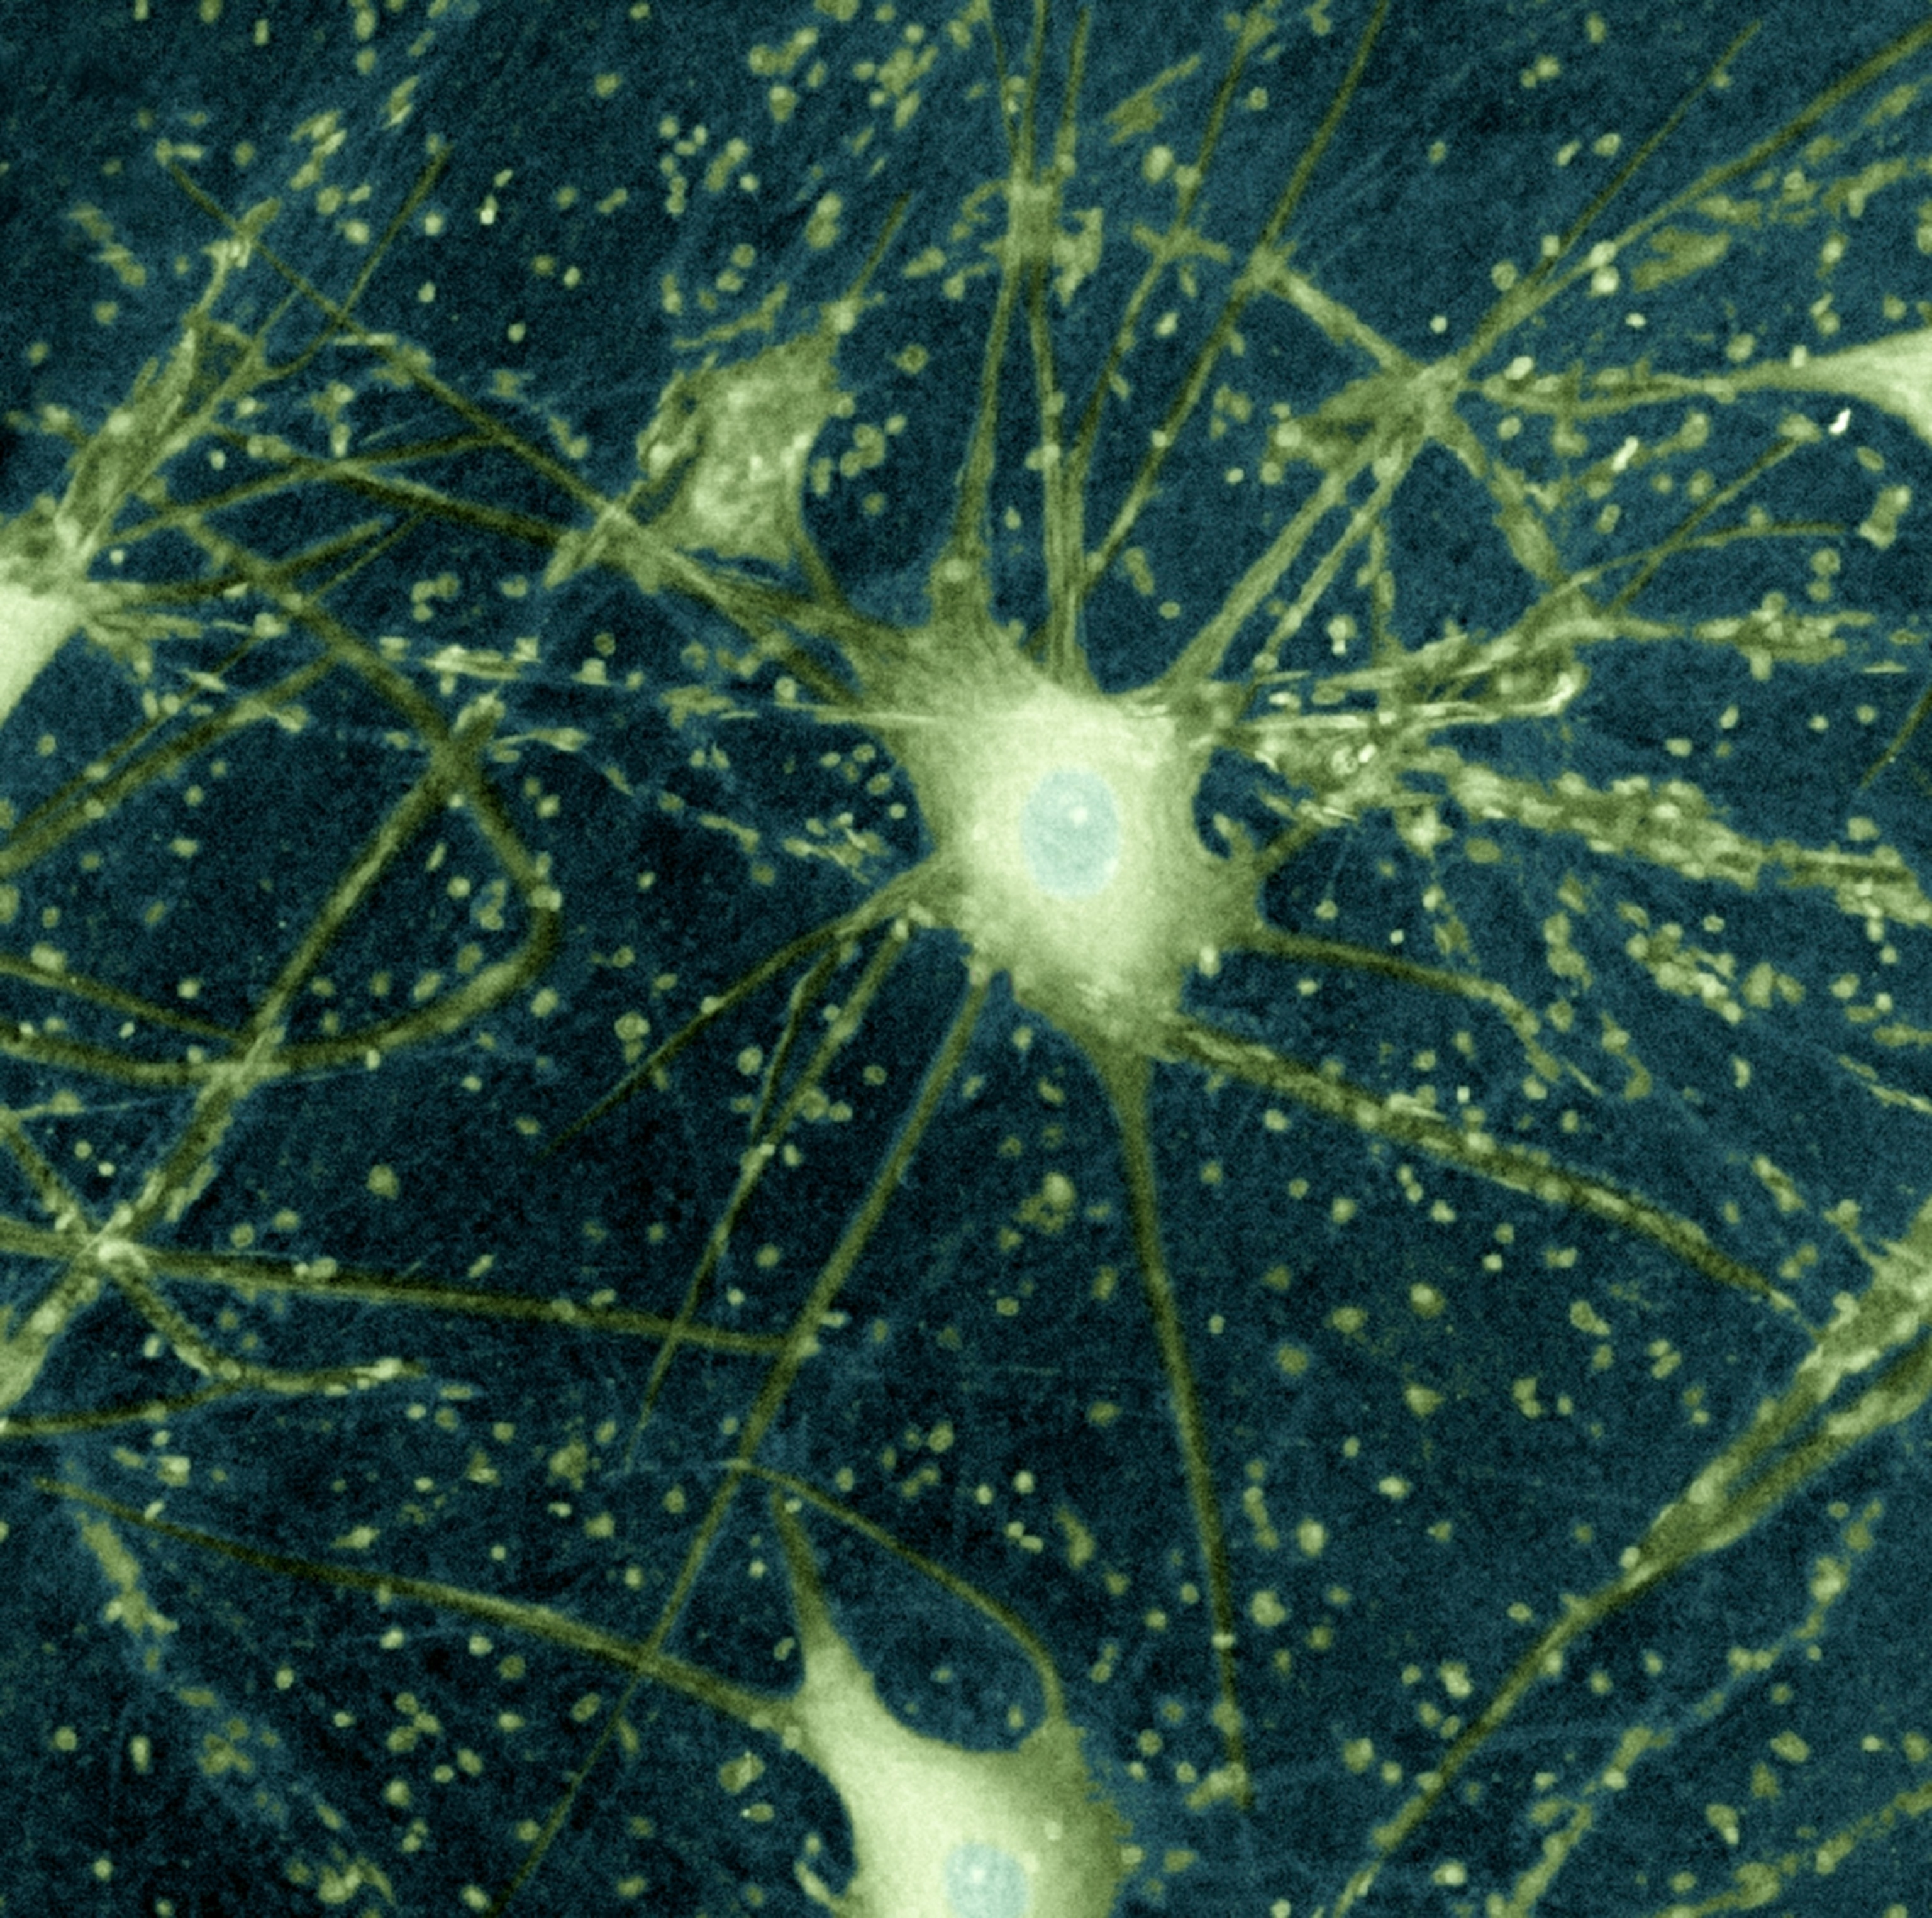

ALS, or amyotrophic lateral sclerosis, is a disease that degrades nerve cells in the brain and spinal cord over time, leading to loss of muscle control and and, ultimately, inability to talk, move, eat, and breathe. Also known as Lou Gehrig’s disease, ALS affects more than 31,000 people in the United States, estimates show; most live only two to five years after symptoms develop.